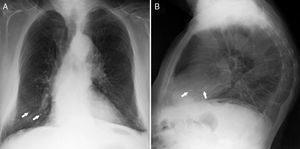

Vertebroplasty was performed in July 2007 and during the procedure surgeons detected a small cement leakage into the vena cava and the right pulmonary artery. The patient remained asymptomatic after vertebroplasty, without developing signs of hypoxemia and pulmonary hypertension. However, the control chest X-ray after the procedure showed radiopaque lesions on the vessels of the lower third of the right lung, which on CT corresponded to multiple emboli of cement in the distal branches of the right pulmonary artery in the middle and lower lobes (Figs. 1 and 2). The patient had no pain after the procedure and was asymptomatic from the respiratory standpoint; however, the cement emboli remained unchanged and are still observed in radiological controls to date.

Because CPE after vertebroplasty is not a rare event and since most cases are initially asymptomatic, the routine performance of a chest X-ray is recommended after the procedure, and even the performance of CT scans for early detection of cement emboli in the pulmonary circulation. In X-rays such emboli may be seen as multiple tubular or branched radiopacities. Computed tomography is the test of choice to confirm their presence, distinguished from other calcified lesions due to their location in areas of branching and the accompanying high attenuation areas around the pulmonary arteries. Echocardiography may be useful in assessing the development of pulmonary hypertension in patients with symptomatic or multiple emboli. In these patients, respiratory function tests may also show decreased CO2 lung diffusion capacity.20